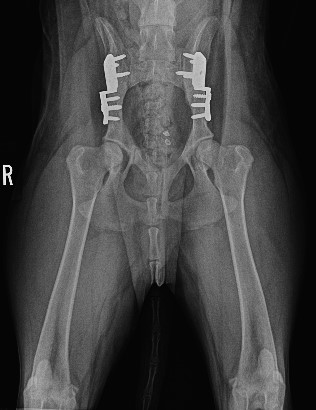

ADVANCED VETERINARY ORTHOPEDIC SERVICES

Our world-class, board-certified veterinary surgeons are dedicated to providing the most advanced canine orthopedic veterinary surgery and musculoskeletal assessment to ensure your beloved pet receives the most appropriate and comprehensive veterinary treatment available.